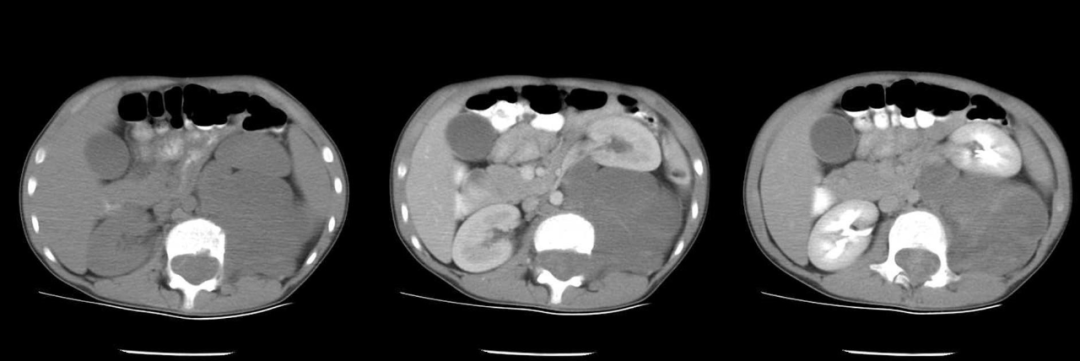

病例二

男,9 岁,因「腹泻、呕吐 2 天,发现腹腔肿物 1 天入院」。

影像描述:右侧肾上腺区见团块样高低混杂密度影,平扫其内见钙化影,大小约 6.6 cm,增强扫描不均匀强化。